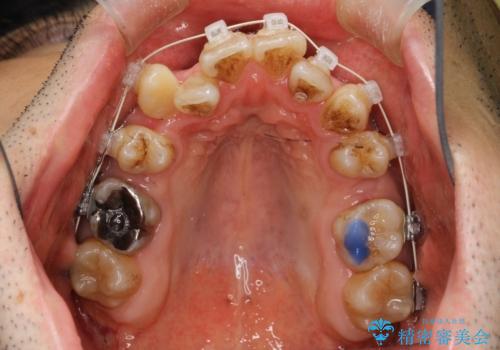

途中までは下顎は全体にワイヤーをはらずに、セクショナルワイヤーにて治療を進めています。

上顎は最初から全体にワイヤーをはっていましたが、上顎前歯部の歯肉退縮のリスクが高そうだったために、途中まで下顎と同じくセクショナルワイヤーで進めています。

八重歯(3番)などは歯肉移植も検討できればよいかなと思います。